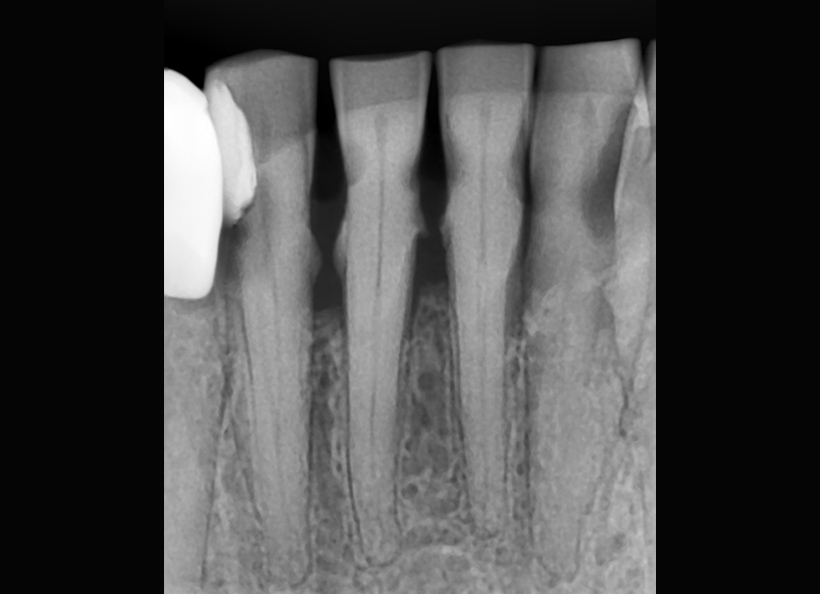

Radiografia digitală retroalveolară dentară este o radiografie digitală care se realizează la unul, maxim doi dinţi. Această radiografie permite medicului stomatolog să vadă în detaliu coroana şi rădăcina întregului dinte, la dimensiuni reale. De obicei această radiografie este indicată când se face un tratament endodontic (se scoate nervul) sau pentru o rezecţie apicală (operaţia rădăcinii dintelui).